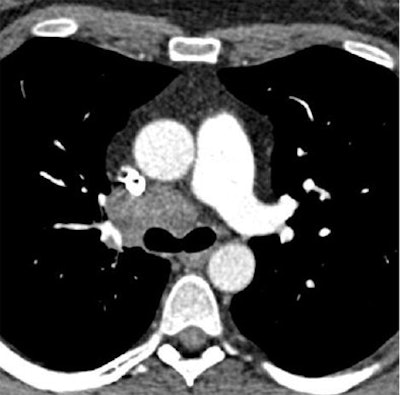

Chest CT exams obtained six months apart in a 40-year-old, obese woman (BMI: 36.5 kg/m2) referred for follow-up of thoracic malignancy. First scan performed with standard dose obtained at the level of the left pulmonary artery, and reconstructed using standard FBP (120 kVp DLP = 326 mGy.cm, Noise = 19.8 HU, and CNR = 8.1) delivers higher noise and radiation dose than low-dose SAFIRE reconstructed image from the same patient six months later, below (100 kVp DLP = 143 mGy.cm, Noise = 17.1 HU, and CNR = 9.2). Despite the dose reduction in the follow-up image, objective image noise measured at the level of the trachea was slightly reduced, and the contrast-to-noise ratio was slightly improved. Images courtesy of Dr. Julien Pagniez and Dr. Martine Rémy-Jardin.